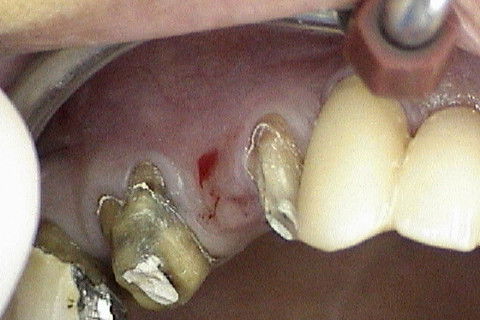

Aspecto clinico da região anterior da maxila 6 meses após o enxerto

Abertura do retalho e inicio da remoção dos parafusos de osteossíntese na região 12

Abertura do retalho e inicio da remoção dos parafusos de osteossíntese na região 22